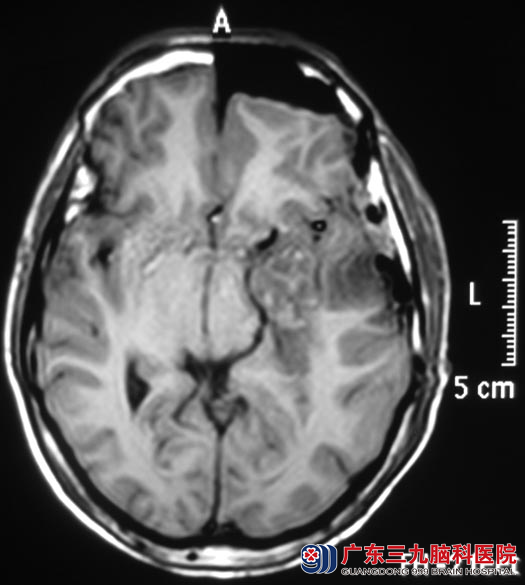

为寻求更专业的治疗,严先生入住广东三九脑科医院综合神经外科。头颅MR检查提示左侧颞叶占位性病变,局部轻度强化,考虑低级别胶质瘤,以弥漫性星型细胞瘤可能性大。

8月1日,鲁明主任主刀,在唤醒麻醉下行左侧颞叶、岛叶占位性病变切除术,术中见肿瘤性质稍韧,血供一般,唤醒麻醉后给予电生理监测,避开语言中枢,在显微镜下予左侧颞叶、岛叶肿瘤切除,术中对大脑前及大脑后动脉保护完好,严先生的语言及肢体运动功能均保护完好,手术顺利结束。复查头颅MRI结果提示:左侧颞叶及岛叶占位基本全切。术后经过治疗,患者康复出院。术后病理结果为:节细胞型胶质瘤(WHO II级)。